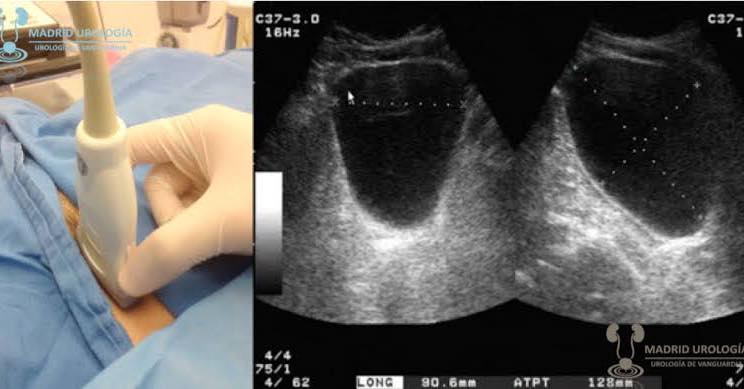

Volumen de orina medido en 3 diámetros por ecografía transabdominal luego de una micción mayor a 125 ml pero menor de 400ml. El RPM es categorizado en: